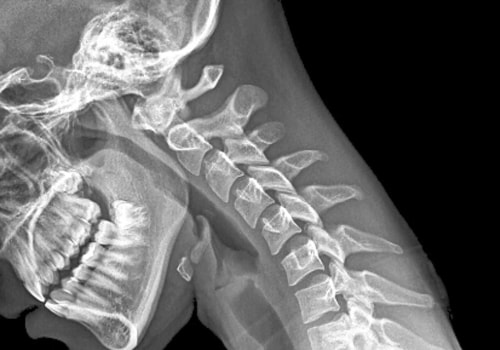

Chiropractic researchers have documented that fraud, abuse and quackery are more common in chiropractic than in other health professions. Neck pain can present as mild discomfort or severe, persistent pain that can be disabling. Because neck pain is often a symptom, a licensed chiropractor will identify the underlying cause and strive to address it through adjustments, physical therapy, and moderate exercise, all of which can positively affect nerves, ligaments, and the blood supply to the head and shoulder area. Restoring the correct function of the vertebrae in the neck and shoulder area helps to relieve spasms muscular.

Low back pain, neck pain, and headaches are the most common reasons people seek chiropractic adjustments. In many cases, such as low back pain, chiropractic care may be a person's primary method of treatment. For some medical conditions, chiropractic services can complement or support medical treatment by alleviating the musculoskeletal aspects associated with the condition. However, as you may have read or heard for yourself, some people consider chiropractic it's a form of pseudoscience.